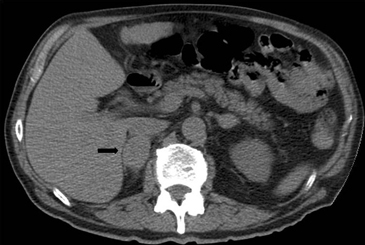

En la TC no contrastada las glándulas suprarrenales normales son homogéneas y simétricas, con una densidad muy similar a la del parénquima renal adyacente (Figura 1 a). Con un medio de contraste ev la glándula suprarrenal se opacifica en forma homogénea, similar al hígado o al bazo (Figura 1 b). Si la cantidad de tejido adiposo retroperitoneal es abundante las glándulas suprarrenales pueden aparecer enteramente rodeadas por grasa y su delimitación es más fácil (Figura 2 a); lo inverso ocurre en pacientes muy delgados con escasa grasa retroperitoneal (Figura 2 b). En RM, en secuencias ponderadas en T1 y T2 convencionales tienen una intensidad de señal homogénea, hipointensa respecto de la grasa adyacente e iso o hipointensa con respecto del parénquima hepático (Figura 3 a y b). En los cortes coronales se aprecia mejor la forma y la posición de las glándulas suprarrenales (Figura 3 c).

Figura 1. Glándula suprarrenal normal en tomografía computada. Cortes axiales de tomografía computada, donde se identifica la morfología normal de la glándula suprarrenal derecha (flecha) en fase no contrastada (a), y tras el uso de medio de contraste endovenoso (b).